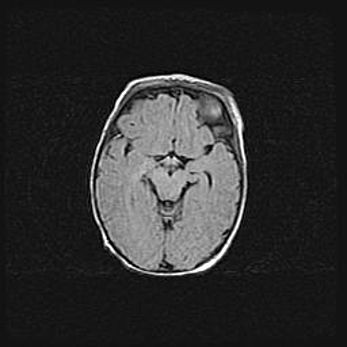

Множественные кисты обоих полушарий головного мозга, наибольшая из них в правой затылочной области. Ассиметричная атрофическая гидроцефалия.

Возраст: 7 месяцев

Вес: 5660 г

Пол: мужской

Окружность головы: 41,5 см

Срок гестации: 28-29 недель

Кисты головного мозга развиваются в результате многоочаговых некрозов вещества мозга и возникают вследствие перенесенной перинатальной инфекции, менингитов, энцефалитов, асфиксии, родовой травмы, расстройств мозгового кровообращения различного генеза. Образованию кист в веществе головного мозга плодов и новорожденных способствуют такие факторы, как высокое содержание в нем воды, недостаточная (или отсутствие) миелинизация и слабая астроглиальная реакция на повреждение.

Кисты могут сочетаться с гидроцефалией и другими поражениями головного мозга.